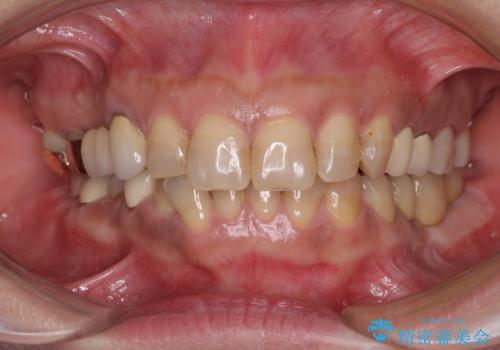

インプラントや歯周外科処置を用いた奥歯の補綴治療

仮歯がない状態を極力避けたいとのことで、外科処置を少しずつ進めていくことになり、治療期間は2年間を要しました。

治療後は痛みなどなく、快適に噛めるようになりました。